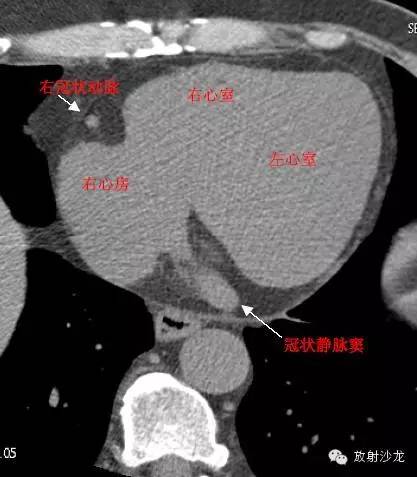

RA -Right Atrium右心房

LV -Left Ventricle左心室

RV -Right Ventricle右心室

RAA –Right AtrialAppendage右心耳

CS -Coronary Sinus冠状窦